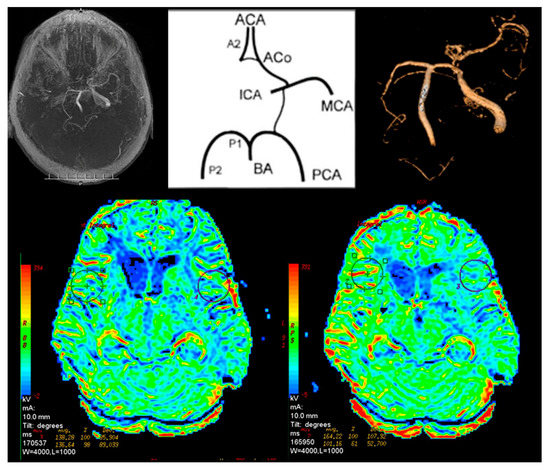

DA—difference Acetazolamide. Difference in the flow between the corresponding ROI points of the symmetrical structures of the left and right hemispheres of the brain, expressed as a percentage (we need only substitute a numerical value in the formula), W index—considered the arteries 1–7 listed in the diagram, HT—hypertension. “1” In the absence of hypertension and “2” in the presence of hypertension (Figure 1).

Figure 1. Arteries of the circle of Willis considered when calculating the W index. ACA—anterior cerebral artery, PCA—posterior cerebral artery, BA—basilar artery, AcoA—anterior communicating artery, PCoA—posterior communicating artery, MCA—middle cerebral artery, ICA—internal carotid artery, A1—1st segment of anterior cerebral artery, A2—2nd segment of anterior cerebral artery, P1—1st segment of posterior cerebral artery, P2—2nd segment of posterior cerebral artery.